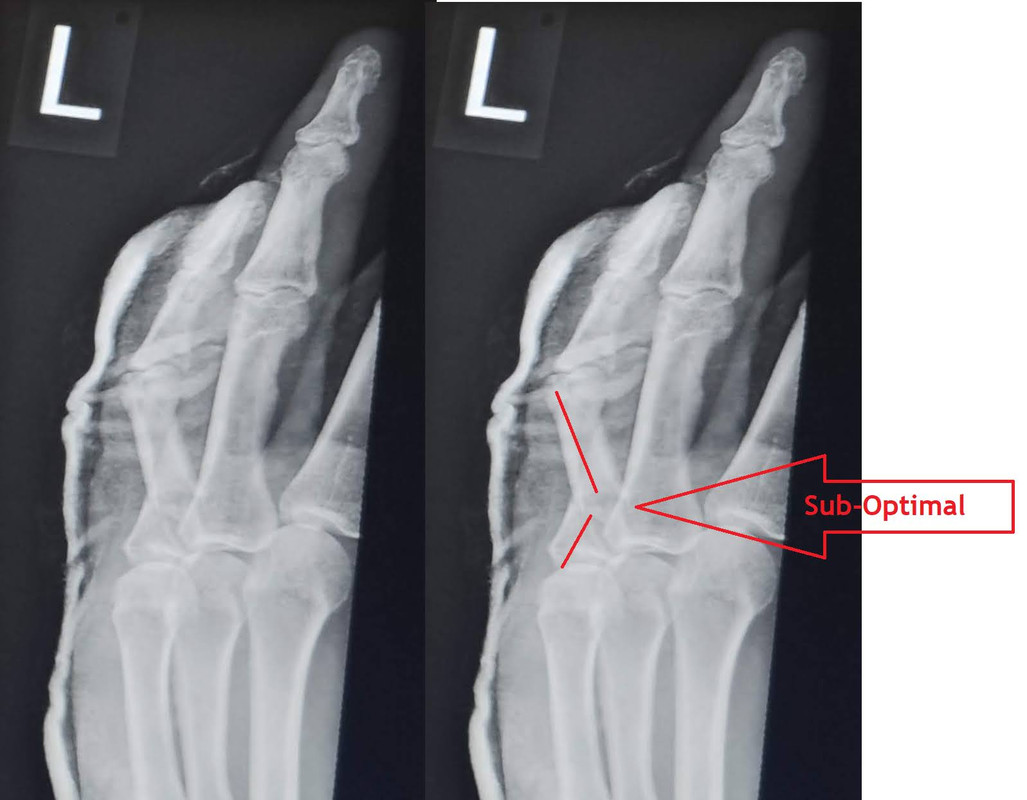

I just noticed that my fingers appear to be drained of blood compare to the rest of my hand which seems a bit strange. I haven't seen them do this before.

That is either Raynauds or a lovely example of episodic stage 2 Vibration white finger blanching.

The fact that it has just occurred, leans it slightly more to the episodic finger blanching that you would expect with vibration damage, if so this is unfortunately irreversible and needs to be managed to prevent further damage and possible loss of function in the hand.

Only vibration was sanding this yesterday. I am not sure if a once over with 80, 120 and then 240 grit is enough but I guess it could be. The fingers have gone normal again now.